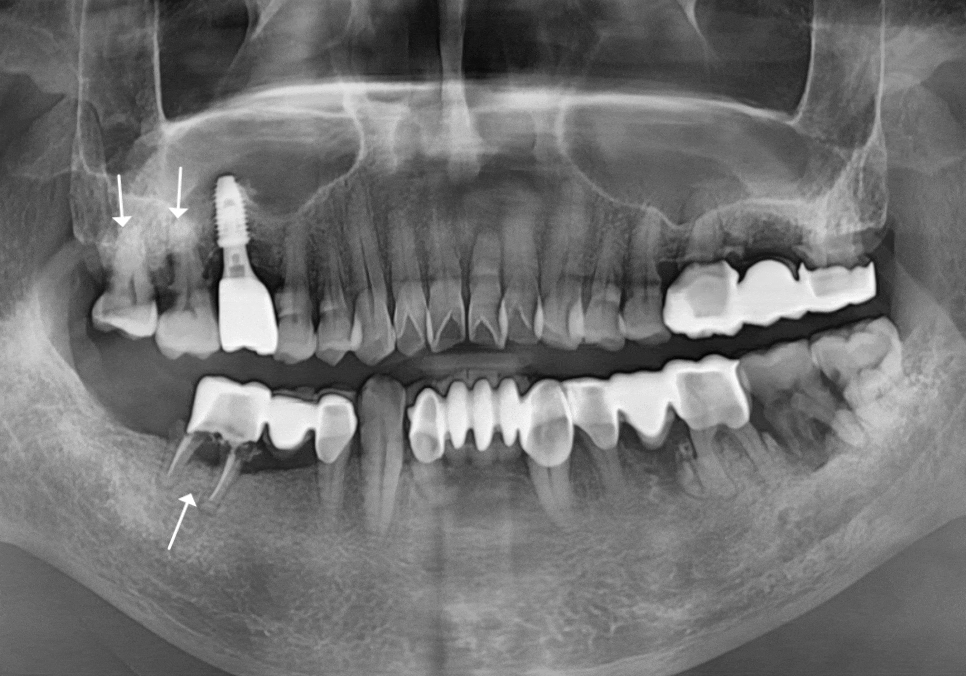

뿐만 아니라, 오른쪽 위 어금니(#18,17) 주변도

염증 때문에 잇몸 뼈가 많이 녹아있는 상태였습니다.

그래서 치주염으로 인해 상태가 좋지 않았던

위쪽 어금니(#18, 17) 부위도

함께 살피기로 했는데요.

고민 끝에 발치를 진행하고

#17번 자리에 임플란트를 식립하기로 했습니다.

다만 위쪽은 잇몸 뼈가

다소 부족한 상태여서

상악동 거상술이라는 정교한 과정을 통해

뼈를 든든하게 보강한 뒤

임플란트를 심기로 했어요.

상악동 거상술을 함께 했던 위쪽 치아는

조금 더 여유를 두었습니다.

4개월 뒤에 튼튼하게 자리 잡은 것을 확인하고

보철물을 올려 마무리해 드렸습니다.